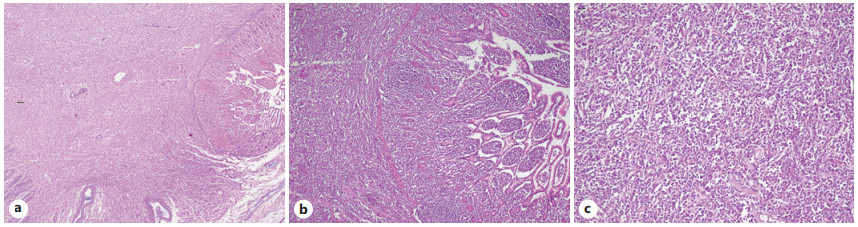

Abstract: Gastrointestinal mast cell sarcoma is a rare variant of mastocytosis. It is a unifocal tumor with high destructive capacity and metastatic potential. Diagnosis of mast cell sarcoma can be challenging and might be so delayed that unfavorable prognosis may be expected. In this case report, we will describe our experience with a case of mast cell sarcoma in the small intestine of an elderly woman, which was diagnosed early on throughout the course of her disease and successfully treated. The patient was a 59-year-old woman who presented with abdominal pain, flushing, weight loss, and vomiting. Imaging studies supported the existence of an infiltrative neoplasm in the jejunum. Then, surgical removal of the tumor was performed. The presence of mast cells in the resected tumor was confirmed by immunohistochemistry, histopathology, and Giemsa staining. After almost a year of follow-up, the patient’s overall condition was fine, and no signs of recurrence were found. This is the first reported case of successfully treated gastrointestinal mast cell sarcoma. All of the previously reported cases had been diagnosed after recurrence with no response to treatment. Our case shows the significance of early diagnosis and treatment in this condition and its impact on outcome and prognosis. That could be achieved only if the pathologist has a high suspicion for this rare disease and keeps it in the back of one’s mind.